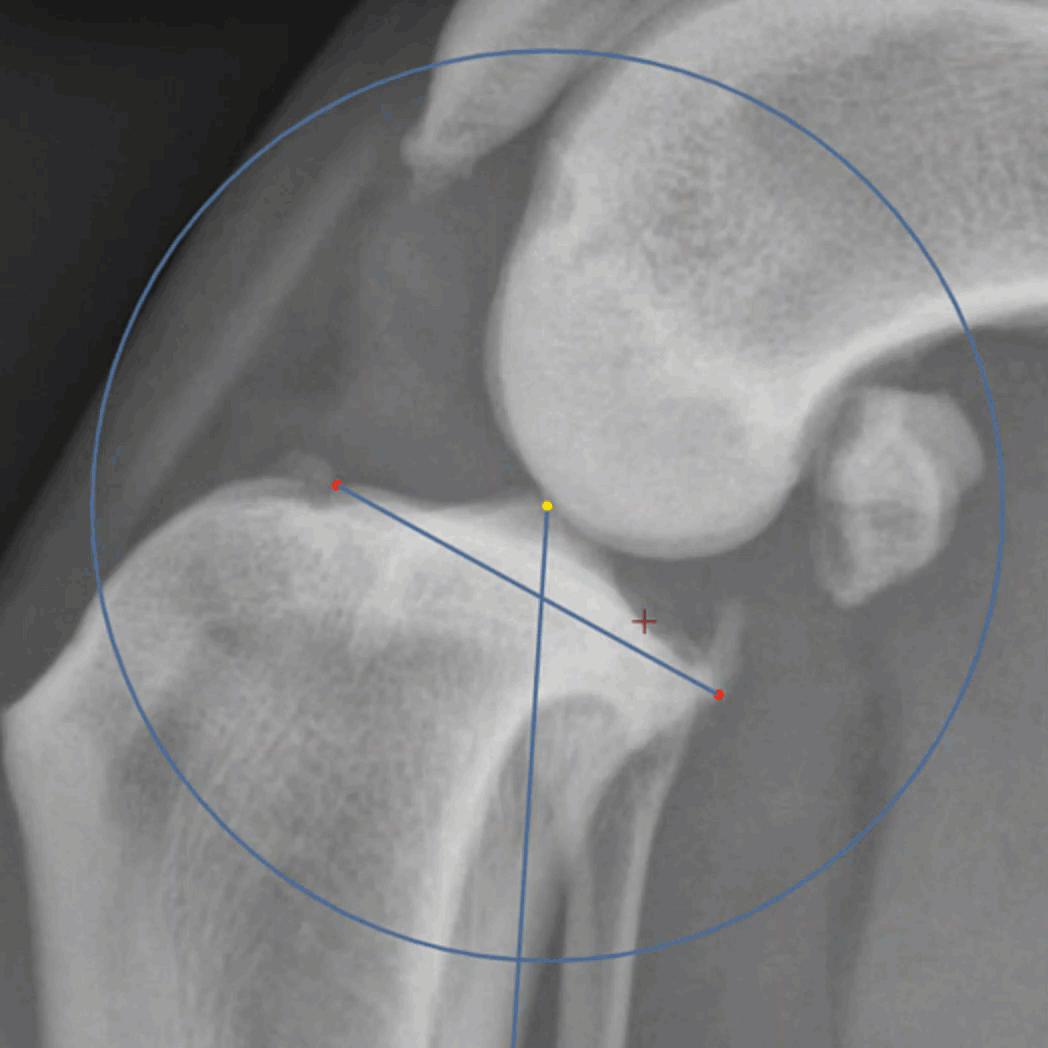

The Freehand Cut tool uses a simple click and drag around perimeter of the fragment to be cut. The cut path with follow the path of the mouse. Release the mouse near the beginning and grab points will automatically be placed and the cut is complete.

As with all of the cutout tools, the center of rotation can be modified and the 0 degree marker is the grab point from which the cut shape will rotate. click within the shape and drag to move the fragment within the viewport.